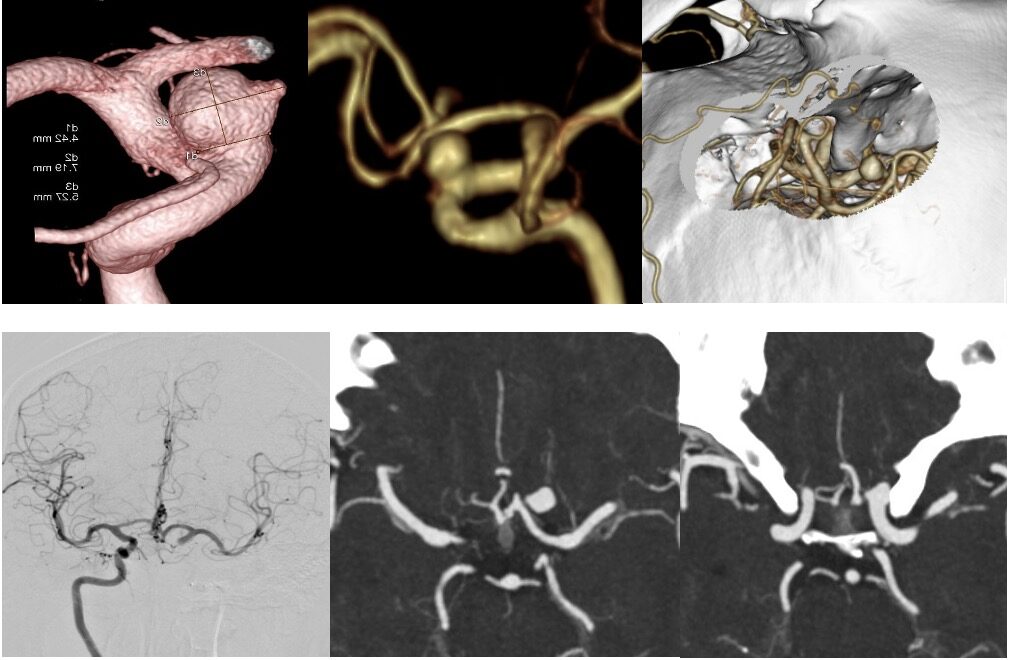

最近のこの場所の動脈瘤クリッピング術が増えています。4mm以上の上向き動脈瘤で術前BTOで虚血耐性のあるものを適応としています。ICG、MEP、VEG、術中血管撮影など術中画像、電気生理学モニタリングをしっかり準備して行っています。本例も視神経下面と癒着しており、剥がすときに破れましたが、問題なくクリップできています。術後の視機能も良好でした。

術後嗄声と2/23より髄液鼻漏れがあり、CTで左篩骨洞に髄液貯留があり5日間の腰椎ドレナージを行い、治癒しました。